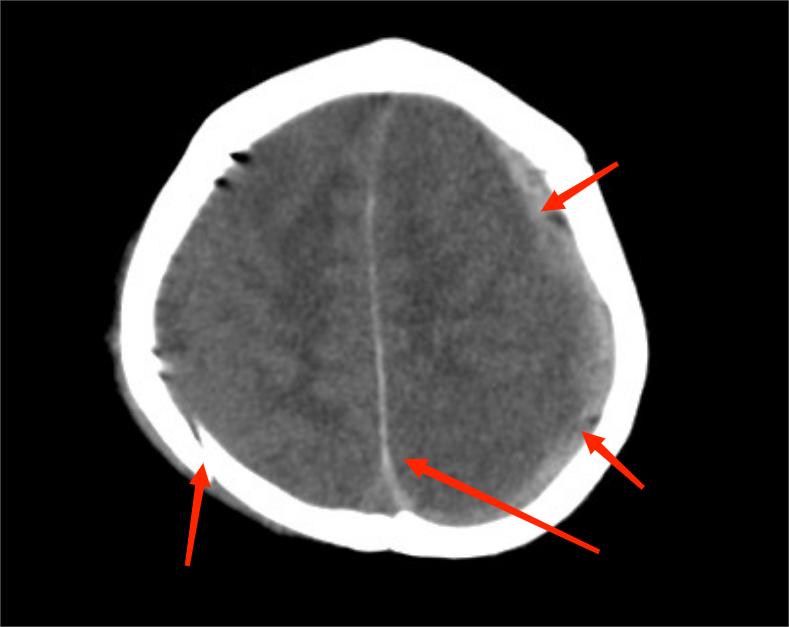

在急诊抢救室,医生发现小尹“双侧瞳孔不等大,对光反射消失”,结合昨天下午她有“摔伤后脑勺”病史,医生判应该“急性颅内出血所致脑疝可能”,紧急查头颅CT提示“硬膜下血肿可能,大脑镰下疝、左侧颞叶钩回疝可能,大脑镰、小脑幕密度增高,蛛网膜下腔出血,枕骨、顶骨骨折,头皮软组织稍肿胀”,考虑“考虑创伤性脑疝”。

因为父母不在身边,爷爷奶奶又六神无主,紧急和其父母电话沟通后,爷爷奶奶代签字后急诊医生马上对小尹进行“脑膜切开伴硬脑膜下腔血肿清除术+筋膜成形术+颅骨去骨瓣减压术”等处理。手术过程顺利,但是未来如何,还要继续住院观察。但是,这对于充满自责和愧疚的小尹爷爷奶奶来说,已经是个好消息了。